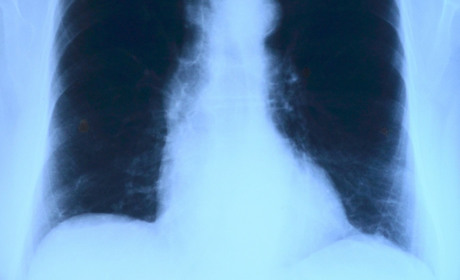

Район В Новотошковском выявлены случаи заболевания туберкулезом: работает передвижной флюорограф 24 жовтня 2018 3916